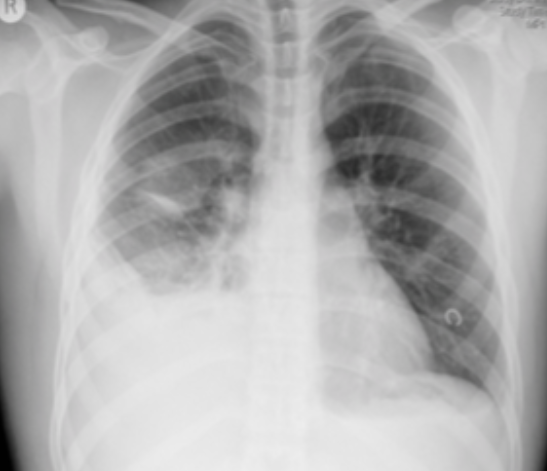

55yo female with known breast cancer develops sudden onset dyspnoea associated with pleuritic chest pain. On questioning she admits to having unilateral calf pain prior to this

PE